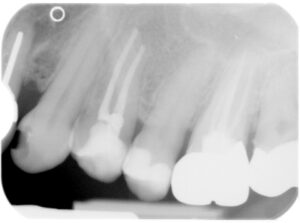

Wie wurde das Problem gelöst?

Im Rahmen einer Wurzelspitzenresektion hat man sich durch einen kleinen Schleimhautschnitt ein Zugang zur Zyste und der Wurzelspitze geschaffen. Die Zyste wurde entfernt, die Wurzelspitze gekappt und die Wurzelfüllung erneuert. Das erste Röntgenbild zeigt den Zustand direkt nach dem Eingriff. Ein Jahr später (zweites Bild) ist der durch das Zystenwachstum entstandene Knochendefekt wieder vollständig ausgeheilt. Darüber hinaus sind die Wurzelspitzen des ursächlichen Zahnes und des Zahnes rechts davon wieder annähernd parallel.